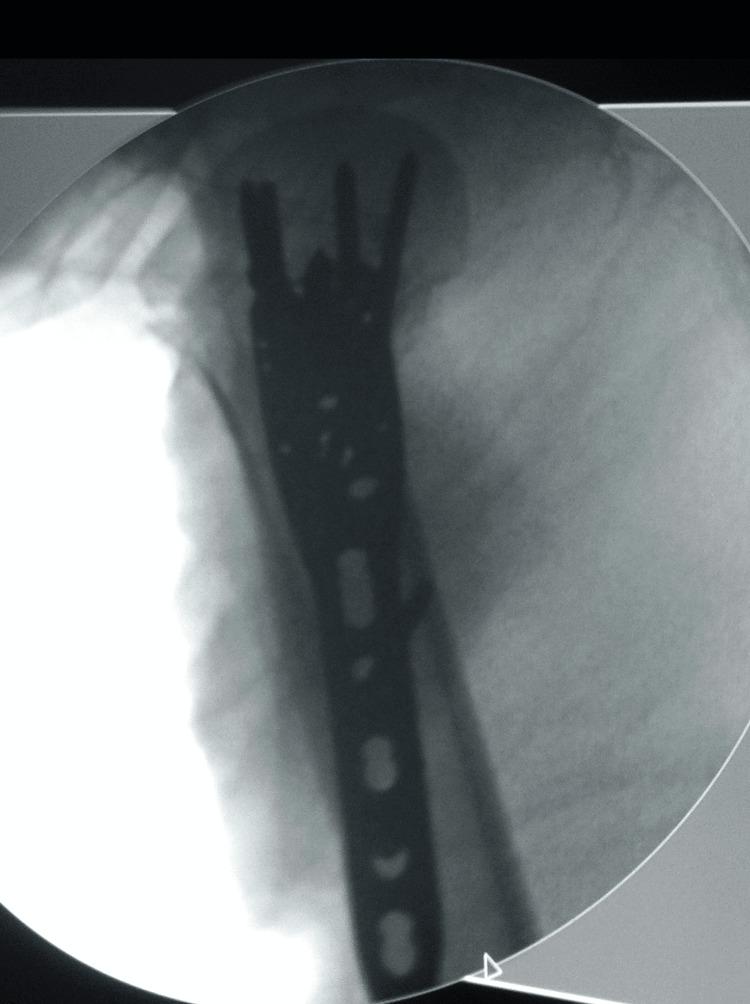

Surgical Fixation of Three- and Four-Part Proximal Humeral Fractures Using the Proximal Humeral Interlocking System Plate.

Introduction The management of proximal humeral fractures ranges greatly from conservative management to surgical treatment. For those fractures requiring surgical treatment, internal fixation is the primary method. The aim of internal fixation is to achieve rigid fracture fixation until union occurs, return of shoulder range of motion, and minimise intra-and postoperative complications. The aim of this study was to evaluate the results of the Proximal Humeral Interlocking System Plate (PHILOS) used for the treatment of three-and four-part proximal humeral fractures. Materials and methods This study included 30 patients with a mean age of 54 years (range 20-80 years). Results were checked post-operatively with standard radiographs and clinical evaluation according to the Constant-Murley shoulder score. All patients were followed up for 12 months. Results Union was achieved in all patients with a mean neck/shaft angle of 130° (range 108°-150°). The mean Constant-Murley score at the final follow-up was 82.28 (range 67-96) correlating with good results. No patients developed an intraoperative or postoperative vascular injury, wound complications, or avascular necrosis of the humeral head. Conclusion Our study has shown that the surgical treatment of three- and four-part proximal humeral fractures with the use of the PHILOS plate leads to a good functional outcome. It has also demonstrated the PHILOS plate and is an effective system for fracture stabilisation provided the correct surgical technique is used with awareness of potential hardware complications.